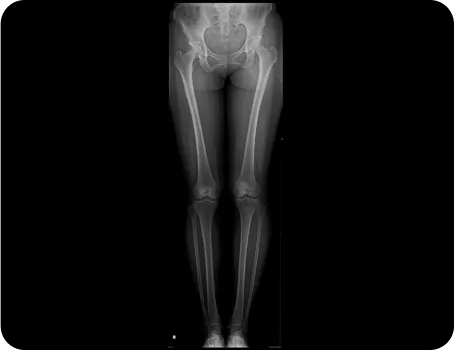

아픈 부위를 촬영한다고 진짜 아픈 원인을 찾을 수 없습니다.

실제 아픈 부위는 피해자일 가능성이 높습니다.

다리 저림이 문제라면 허리디스크 탈출을 의심하듯 무릎의 문제가 틀어진 발목이나 골반 때문일 수 있습니다.

그래서 가해자를 찾는 검사까지 같이 해야 합니다.

부위별 촬영

제대로 된 원인을 찾아 개선하지 않고

통증 부위에만 치료를 반복한다면

재발할 가능성이 높습니다.

전신체형분석 X-선 검사

풀스파인 촬영으로

신체의 전체적인 문제를 파악하고

통증의 정확한 원인을 찾아

재발을 예방하고, 통증을 개선하는

치료를 합니다.